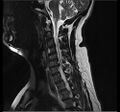

انزلاق غضروفي خلال تمزق في الحلقة (موضح بالتصوير بالرنين المغناطيسي).[9]

- التصوير بالرنين المغناطيسي هي الدراسة المعيارية الذهبية لتأكيد الاشتباه في انزلاق غضروفي. مع دقة تشخيصية تبلغ 97%، فهي الدراسة الأكثر حساسية لتصور الانزلاق الغضروفي بسبب قدرتها الكبيرة على تصور الأنسجة الرخوة. كما يتمتع التصوير بالرنين المغناطيسي بموثوقية أعلى بين المراقبين مقارنة بوسائل التصوير الأخرى. ويشير إلى انزلاق غضروفي عندما يظهر إشارة متزايدة مرجحة بـ T2 عند المنطقة الخلفية التي تغطي 10% من القرص. وقد أظهرت أمراض الانزلاق الغضروفي ارتباطًا بتغيرات النوع 1 من مقياس موديك. عند تقييم اعتلالات الجذور العصبية القطنية بعد الجراحة، فإن التوصية هي إجراء التصوير بالرنين المغناطيسي مع التباين ما لم يكن هناك موانع أخرى. يعد التصوير بالرنين المغناطيسي أكثر فعالية من التصوير المقطعي المحوسب في التمييز بين الأسباب الالتهابية أو الخبيثة للانزلاق الغضروفي. يُشار إليه في وقت مبكر نسبيًا في مسار التقييم (<8 أسابيع) عندما يظهر المريض مؤشرات نسبية مثل الألم الشديد والعجز الحركي العصبي ومتلازمة ذيل الفرس. التصوير الموتر الانتشاري هو نوع من تسلسل التصوير بالرنين المغناطيسي المستخدم للكشف عن التغيرات الدقيقة في جذر العصب. قد يكون مفيدًا في فهم التغييرات التي تحدث بعد أن يضغط القرص القطني المنفتق على جذر العصب، وقد يساعد في التمييز بين المرضى الذين يحتاجون إلى تدخل جراحي. في المرضى الذين لديهم شكوك عالية في اعتلال الجذور العصبية بسبب الانزلاق الغضروفي القطني، ومع ذلك فإن التصوير بالرنين المغناطيسي غامض أو سلبي، يوصى بدراسات التوصيل العصبي.[44] توفر الصور المرجحة الناتجة عن التصوير بالرنين المغناطيسي (T2) تصور واضح لمادة القرص البارز في القناة الشوكية.